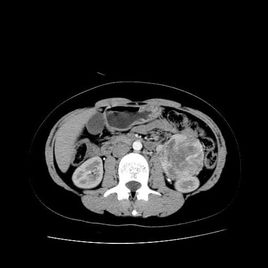

腹膜由單層間皮細(xì)胞及少量結(jié)締組織構(gòu)成。腹膜疾病主要包括腫瘤性病變及炎性病變。腹膜腫瘤性病變可細(xì)分為腹膜原發(fā)腫瘤及腹膜繼發(fā)腫瘤。腹膜繼發(fā)腫瘤的發(fā)病率遠(yuǎn)高于腹膜原發(fā)腫瘤。腹膜繼發(fā)腫瘤包括腹膜癌性轉(zhuǎn)移、腹膜假性黏液瘤、腹膜淋巴瘤及腹膜肉瘤性轉(zhuǎn)移。